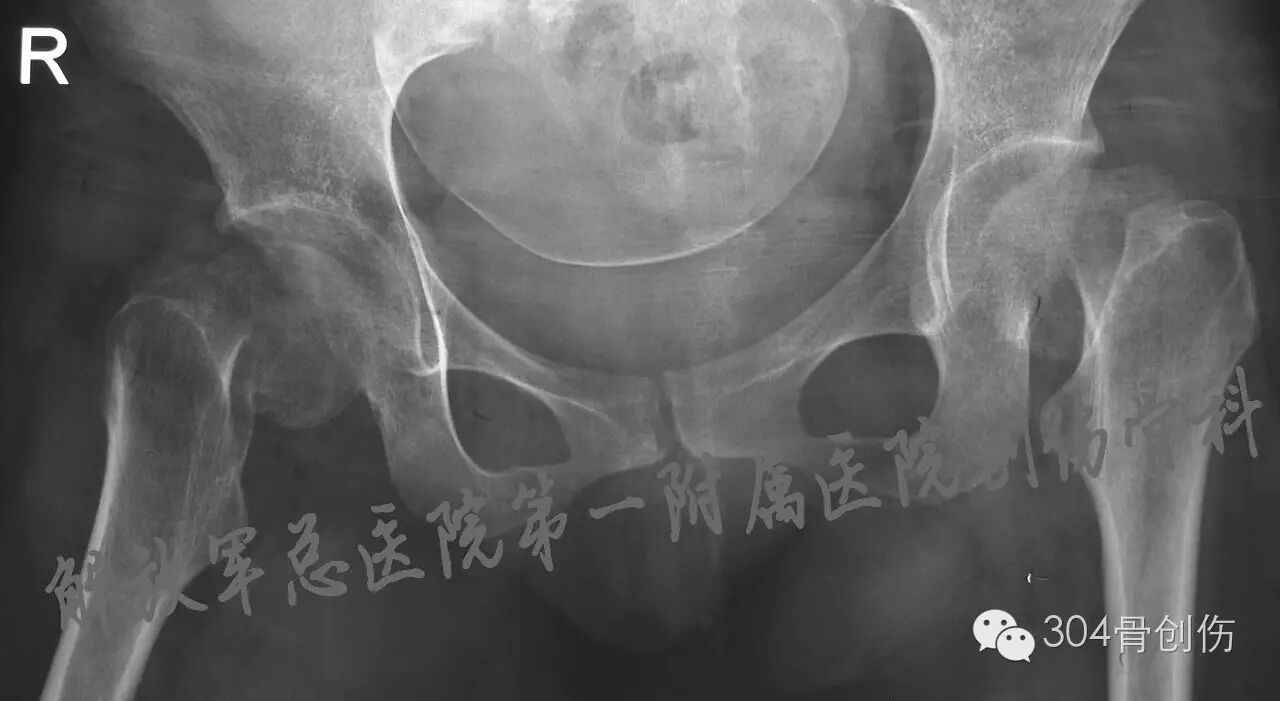

髋部一过性骨质疏松症(transient osteoporosis of the hip, TOH)是出现于妊娠晚期的一种罕见的骨代谢紊乱状况,其病因不清楚,表现为髋部疼痛及活动受限,可在髋关节X线上观察到明显骨量减少,1959年Curtiss教授首次报道(图),2005年国内郭依廷医生首次报道(图),综合发病过程,定义为“妊娠期一过性骨质疏松症”,不完全统计:全世界报道大约100余例,多为脊柱骨折,双侧股骨颈骨折少见,陈旧股骨颈骨折处理极为困难,目前缺乏大宗相关文献报道。

①常发生在妊娠末三个月,产后2个月内恢复;②轻度外伤即可导致髋部疼痛及活动受限;③X线检查可见明显的单侧或双侧髋部骨质密度减低,同时可见髋部骨折,MRI T1加权像示骨髓信号强度减弱,而T2加权图像的信号强度增加;④与骨质疏松相关的生化指标,如血沉增快和尿羟脯氨酸水平升高等(本病例未见明显异常);⑤骨密度降低。